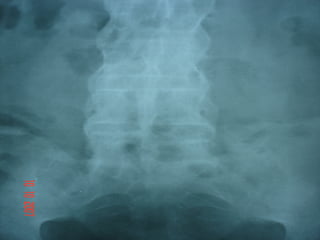

Alterações radiológicas

Quadratura dos corpos vertebrais

Coluna em bambu

sindesmófitos vertebrais

discite

osteítes

alterações das sacro-ileítes:borramento do osso

subcondral,pseudo-alargamento,erosões e esclerose

Quadratura de vértebras + ângulos brilhantes